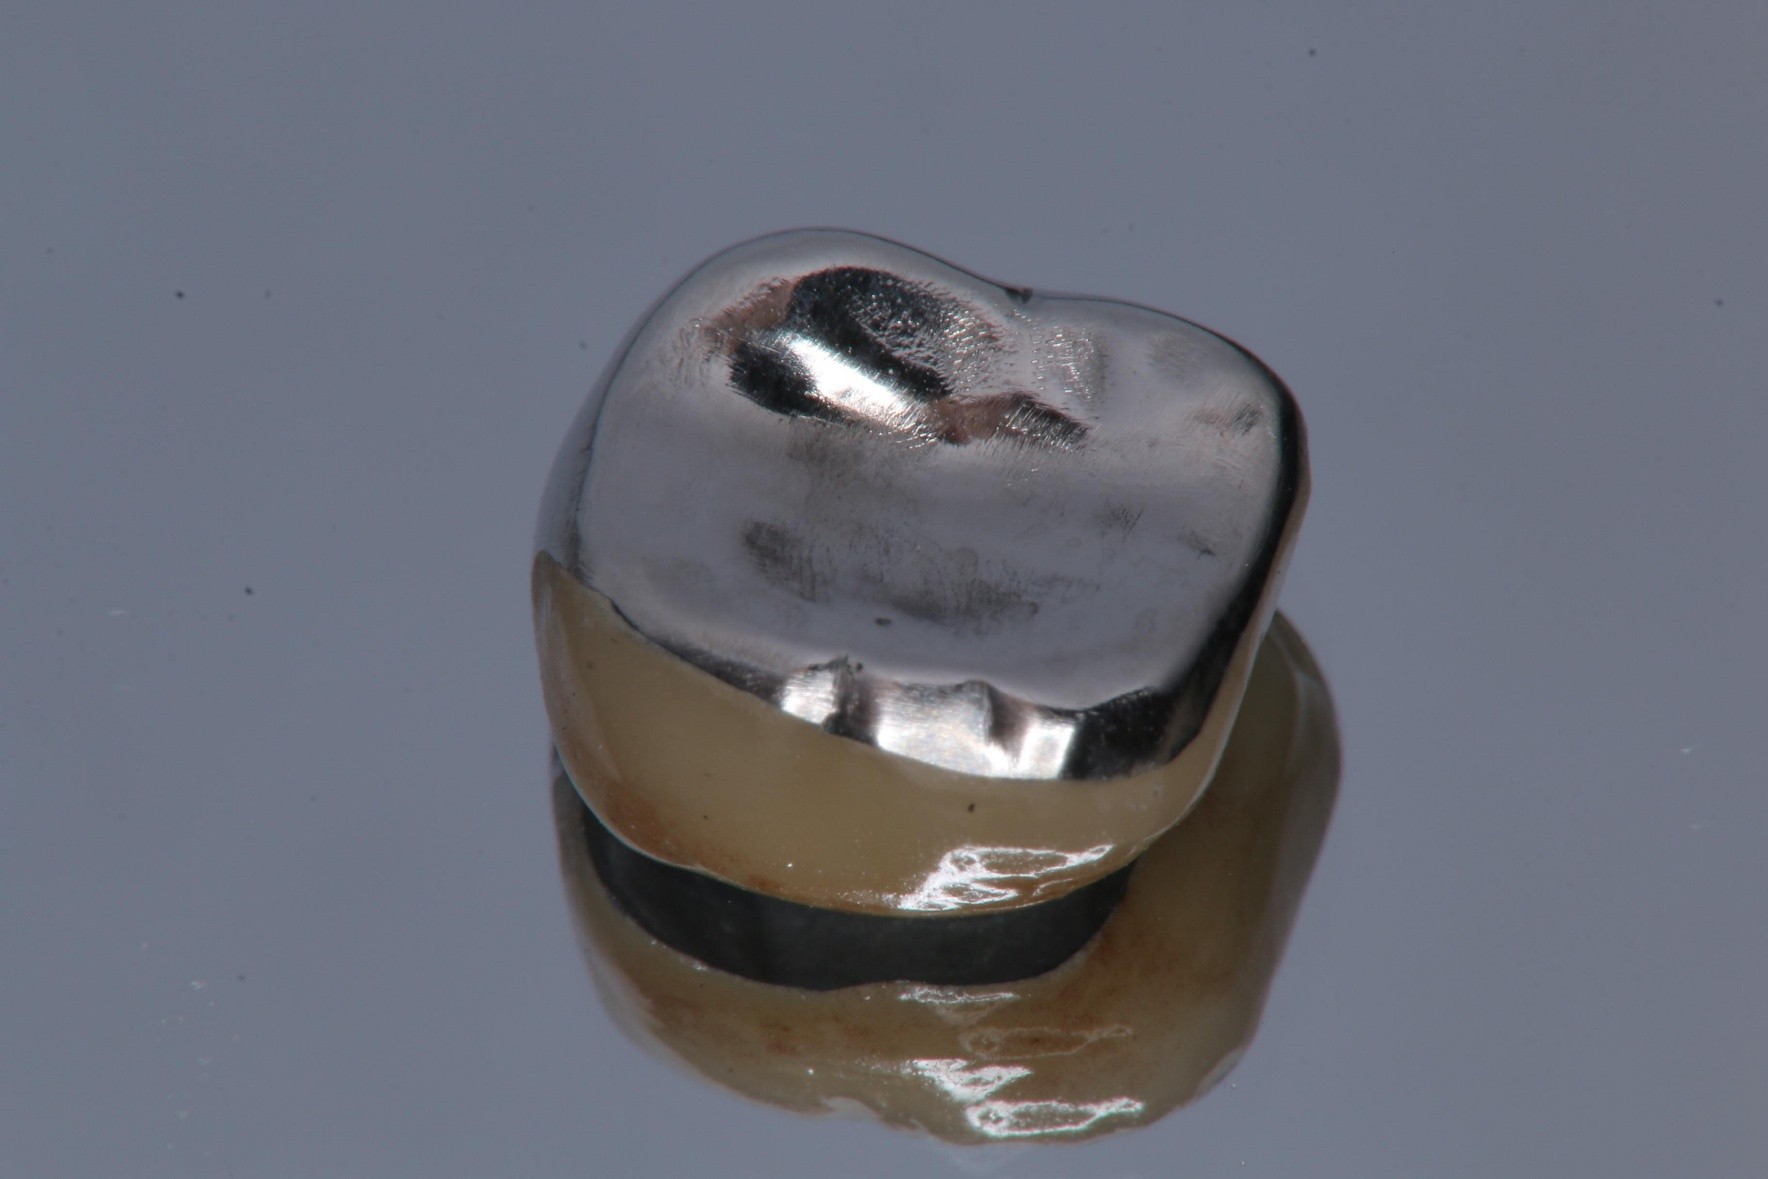

製作金屬燒付瓷牙:牙技師會根據印模製作出金屬燒付瓷牙,其外層是陶瓷,內層是金屬。

因受力考量,製作金屬燒付瓷牙